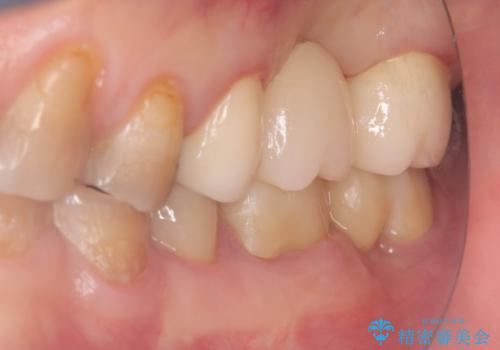

左上7番遠心マージン不適を認め、そこに汚れが停滞していたためやり替えをおすすめし、汚れが付着しずらく審美性に優れたセラミッククラウンブリッジでのやり替えとなりました。

保険適用のメタルインレーを除去したところ、ポンティック部の過度な加圧によって歯肉が強く発赤していたため、一度仮歯に置き換え歯肉の治りを待った後、適切な加圧強さのオールセラミッククラウンブリッジをセットしています。